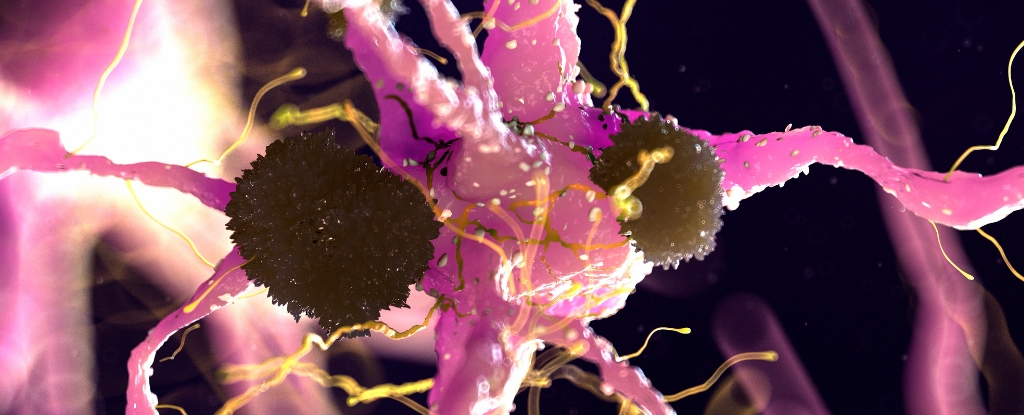

A team of researchers at Florida International University (FIU) has uncovered a potential early indicator of Alzheimer’s disease linked to a brain protein. This breakthrough could pave the way for identifying neurodegeneration years before symptoms typically manifest. The study focused on the translocator protein 18 kDa, or TSPO, previously associated with inflammation in Alzheimer’s patients.

In experiments using mouse models, researchers found that elevated levels of TSPO appeared as early as six weeks, which corresponds to approximately 18 to 20 human years. These increased levels were particularly noted in the subiculum, an area of the brain vital for memory formation. This discovery raises the possibility of using TSPO as a biomarker for early detection of Alzheimer’s.

The study revealed that female mice exhibited higher levels of TSPO, reflecting existing data that suggests women are more susceptible to developing Alzheimer’s. Additionally, the rise in TSPO levels coincided with the emergence of amyloid-beta plaques, which are protein clumps associated with the disease. Notably, the increase in TSPO was primarily found in immune cells known as microglia, which had responded to the plaque accumulation.

The findings provide crucial insights into the origins of Alzheimer’s, presenting clues about the chemical reactions that might help slow or halt its progression. Guilarte pointed out that microglia appear to play a central role in the inflammatory response: “What we believe is happening is something goes wrong with the microglia. They stop doing their job in removing the plaques and just keep sending out TSPO signals. This constant signal of neuroinflammation is like adding wood to a fire.”